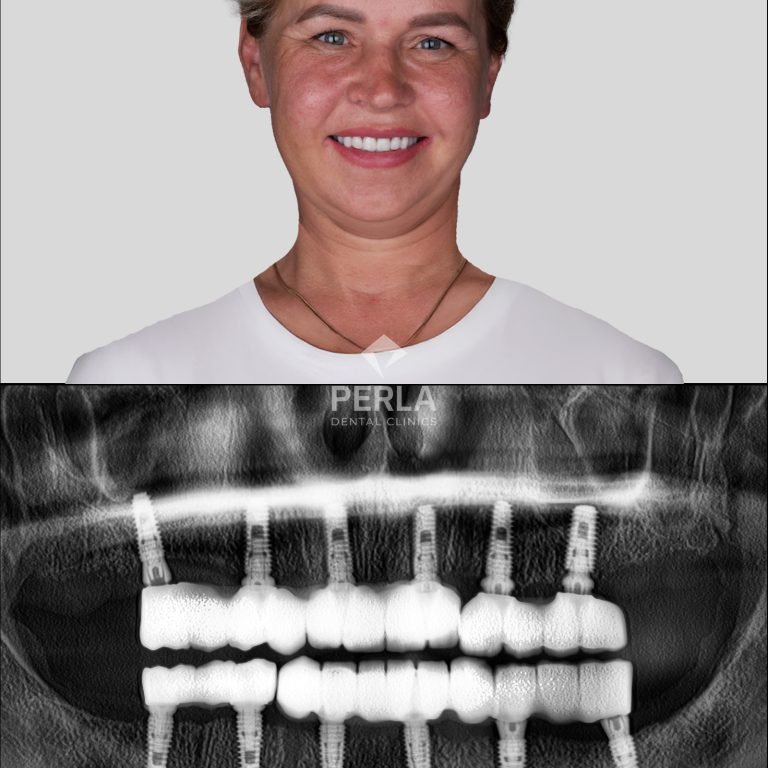

Why Choose All-on-4 Dental Implants?If you're considering dental implants, All-on-4 offers a remarkable solution that is less invasive …